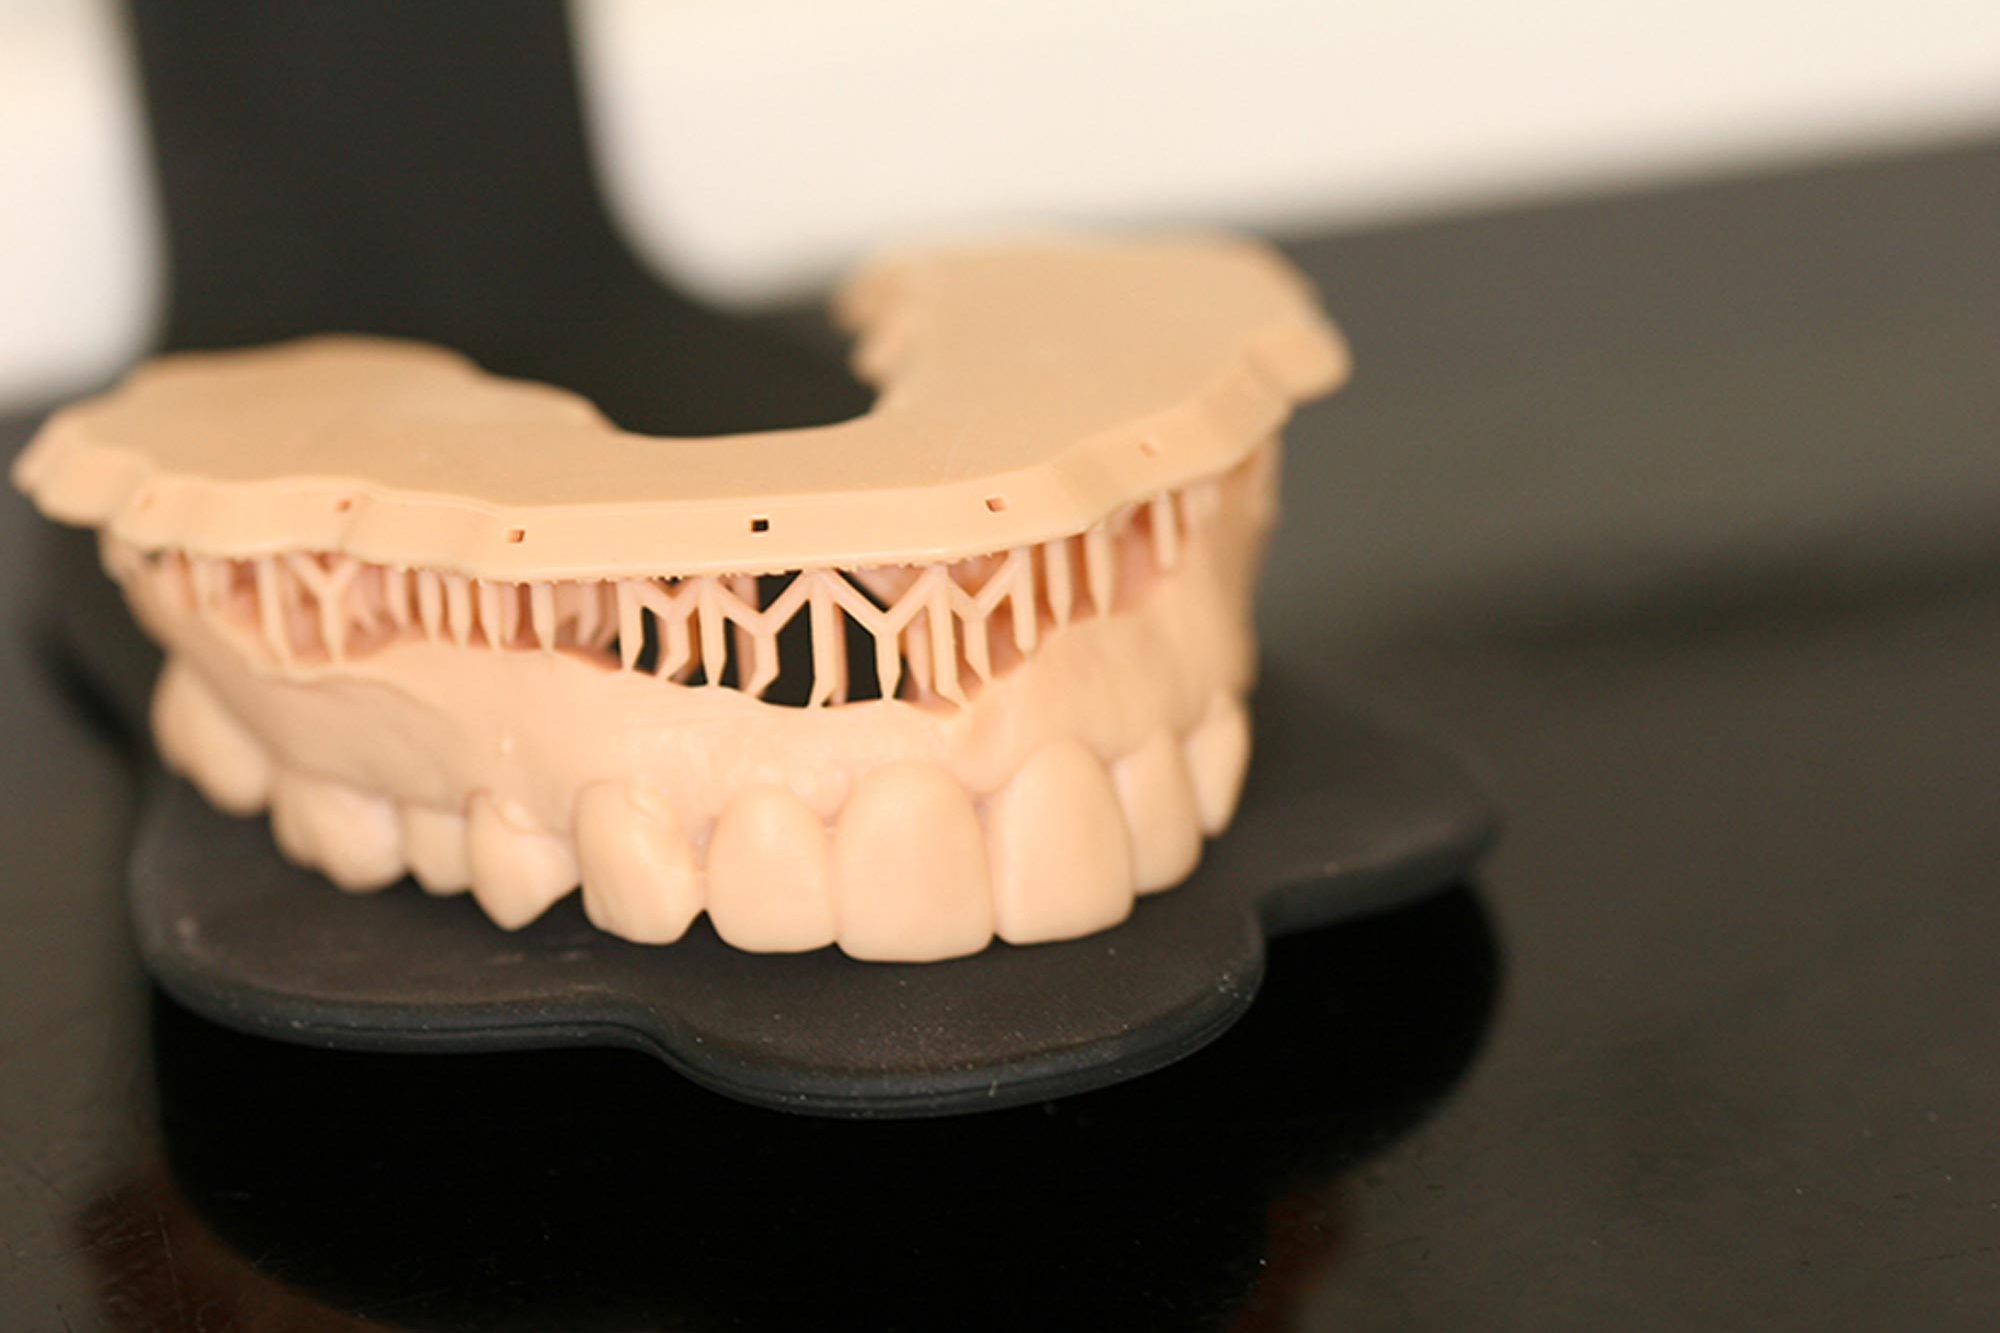

PS attended on the morning of the day of the procedure to have the preparation done. At this time, we 3D printed the mock-up model so she could visualise the predicted final outcome before the prep (Figure 5).

The scanning data was then forwarded to the Wensleydale lab located within the practice and the manufacturing of the crowns followed – shaped using the biocopy of the mock-up and milled on the Sirona Cerec MC XL milling unit from lithium disilicate A3 blocks, followed by glazing and characterisation of the dental anatomy (Figures 5 to 7).